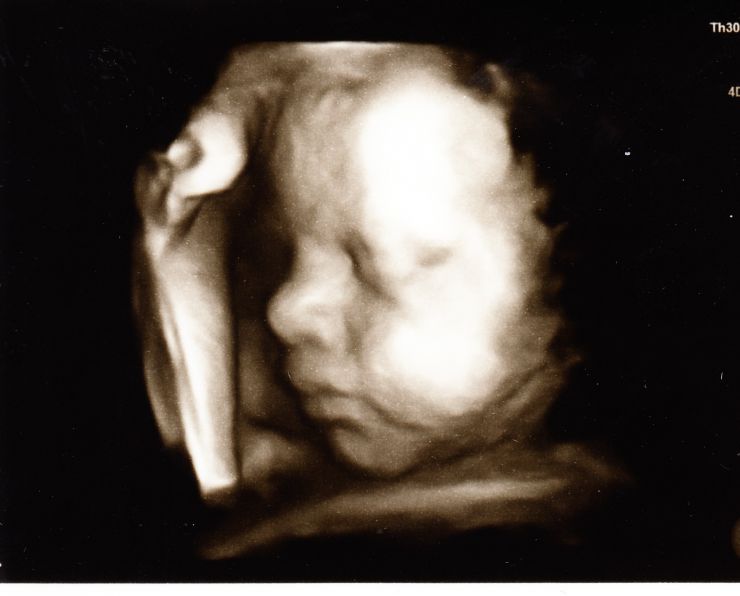

Галерея УЗИ 3D/4D . Записаться на прием . Автор фото: Доктор Сотников Е .И . Плод 31 неделя .

Полученное 3D-фото напоминает голограмму . Ребёнок виден отчётливо, от личика до крохотных пальчиков на руках и ногах . Ряд снимков выстраивается так, что в итоге получается короткое кино . На этой ленте прослеживается мимика малыша и его движения .

10 .03 .2005 УЗИ плода 3D (4D) - Слепченкова Лариса, III триместр беременности . (просмотров: 20916) . 10 .03 .2005 УЗИ плода 3D (4D) - Смирнова Кристина, II триместр беременности . (просмотров: 41314) .